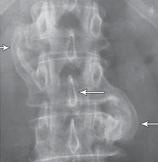

На рентгенограмме № 6 поясничного отдела позвоночника выраженный остеофитоз, спондилёз третьей степени, что также хорошо видно на МРТ № 39 поясничного отдела позвоночника МРТ № 40 ![]() МРТ № 41